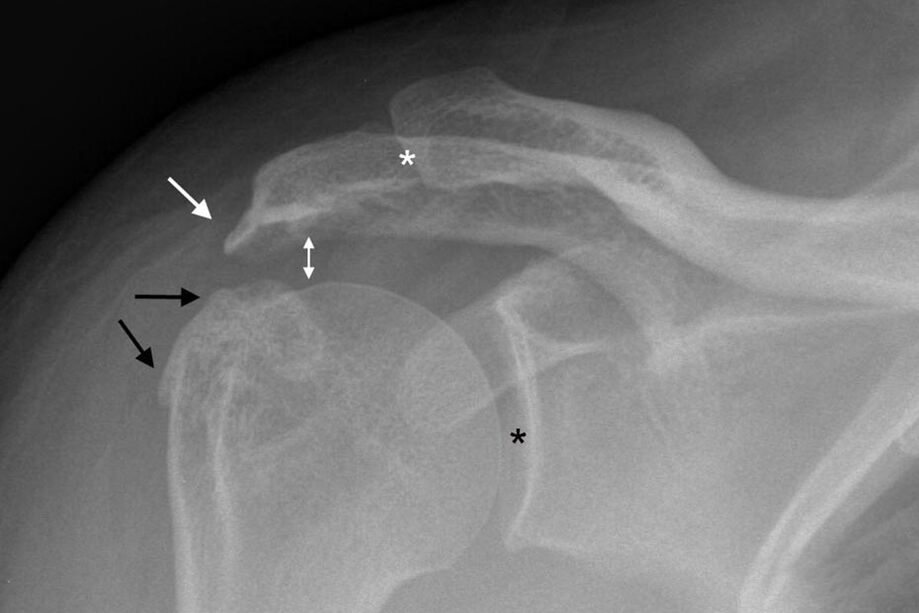

L'arthrose de l'articulation de l'épaule peut être diagnostiquée à l'aide d'une radiographie standard de l'épaule. L'image est prise en deux projections. Le médecin diagnostique la maladie en présence de facteurs tels que :

- Rétrécissement de l'espace articulaire ;

- Formation d'ostéophytes ;

- Sclérose du tissu osseux.

Sous certaines conditions, d'autres méthodes d'étude de l'épaule sont prescrites. Échographie pour déterminer l'épaisseur du cartilage et évaluer l'état des tissus mous.

Si possible, les échographies et les radiographies peuvent être remplacées par une IRM. Il s'agit d'une méthode informative unique pour examiner le corps souffrant d'arthrose. La procédure permet d'évaluer l'état de la structure osseuse, du cartilage et des ligaments et de comprendre comment traiter l'arthrose de l'épaule.